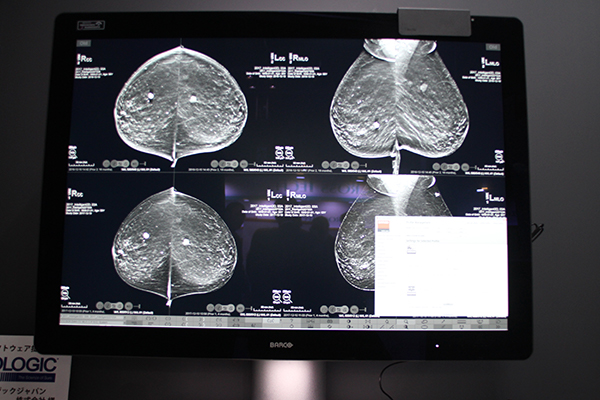

ブースでは,オール・モダリティ医用画像表示ディスプレイ「Coronis Uniti」を展示した。Coronis Unitiは,12メガピクセル,推奨輝度1000cd/m2と,超高解像度,超高輝度を達成したディスプレイで,マンモグラフィを含めたさまざまなモダリティの画像を同時に1台で表示することができる。モノクロ表示(GSDF)とリニアカラー表示を両立し最適な表示環境を提供する“Steady Color”など,画像観察の精度を向上させるさまざまな高画質機能や,精査が必要な患部や病変部分に焦点を合わせて対象エリアを最大輝度に引き上げて視認性を向上する“SpotView”など,画像観察の効率化をサポートする独自の機能を搭載し,日本乳がん検診精度管理中央機構よりマンモグラフィ診断に適合するディスプレイとして認定を取得した。

また,マンモグラフィ用画像表示ディスプレイ「Nio Color 5.8MP」も展示した。Nio Color 5.8MPは,5.8メガピクセルと一般的なマンモグラフィ用画像表示ディスプレイで採用されている5メガピクセルよりも大きな解像度表示をサポートしている。また,カラー表示に対応しているため,マンモグラフィはもちろん,超音波などのカラー画像も1画面で同時に表示できる。Coronis Unitiに搭載されているSteady ColorやSpotViewなどにも対応し,読影効率の向上に貢献する。

両製品は,照明を調整して読影室と同様の環境を再現したダークルームに設置され,実際の読影環境でディスプレイのパフォーマンスを体験できるようにしていた。

12メガピクセルの医用画像表示ディスプレイCoronis Uniti

デジタルマンモグラフィ画像表示用カラーディスプレイNio Color 5.8MP